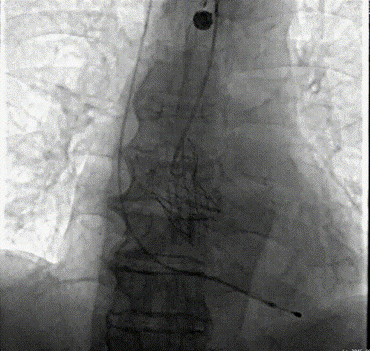

介入瓣置入手术影像。